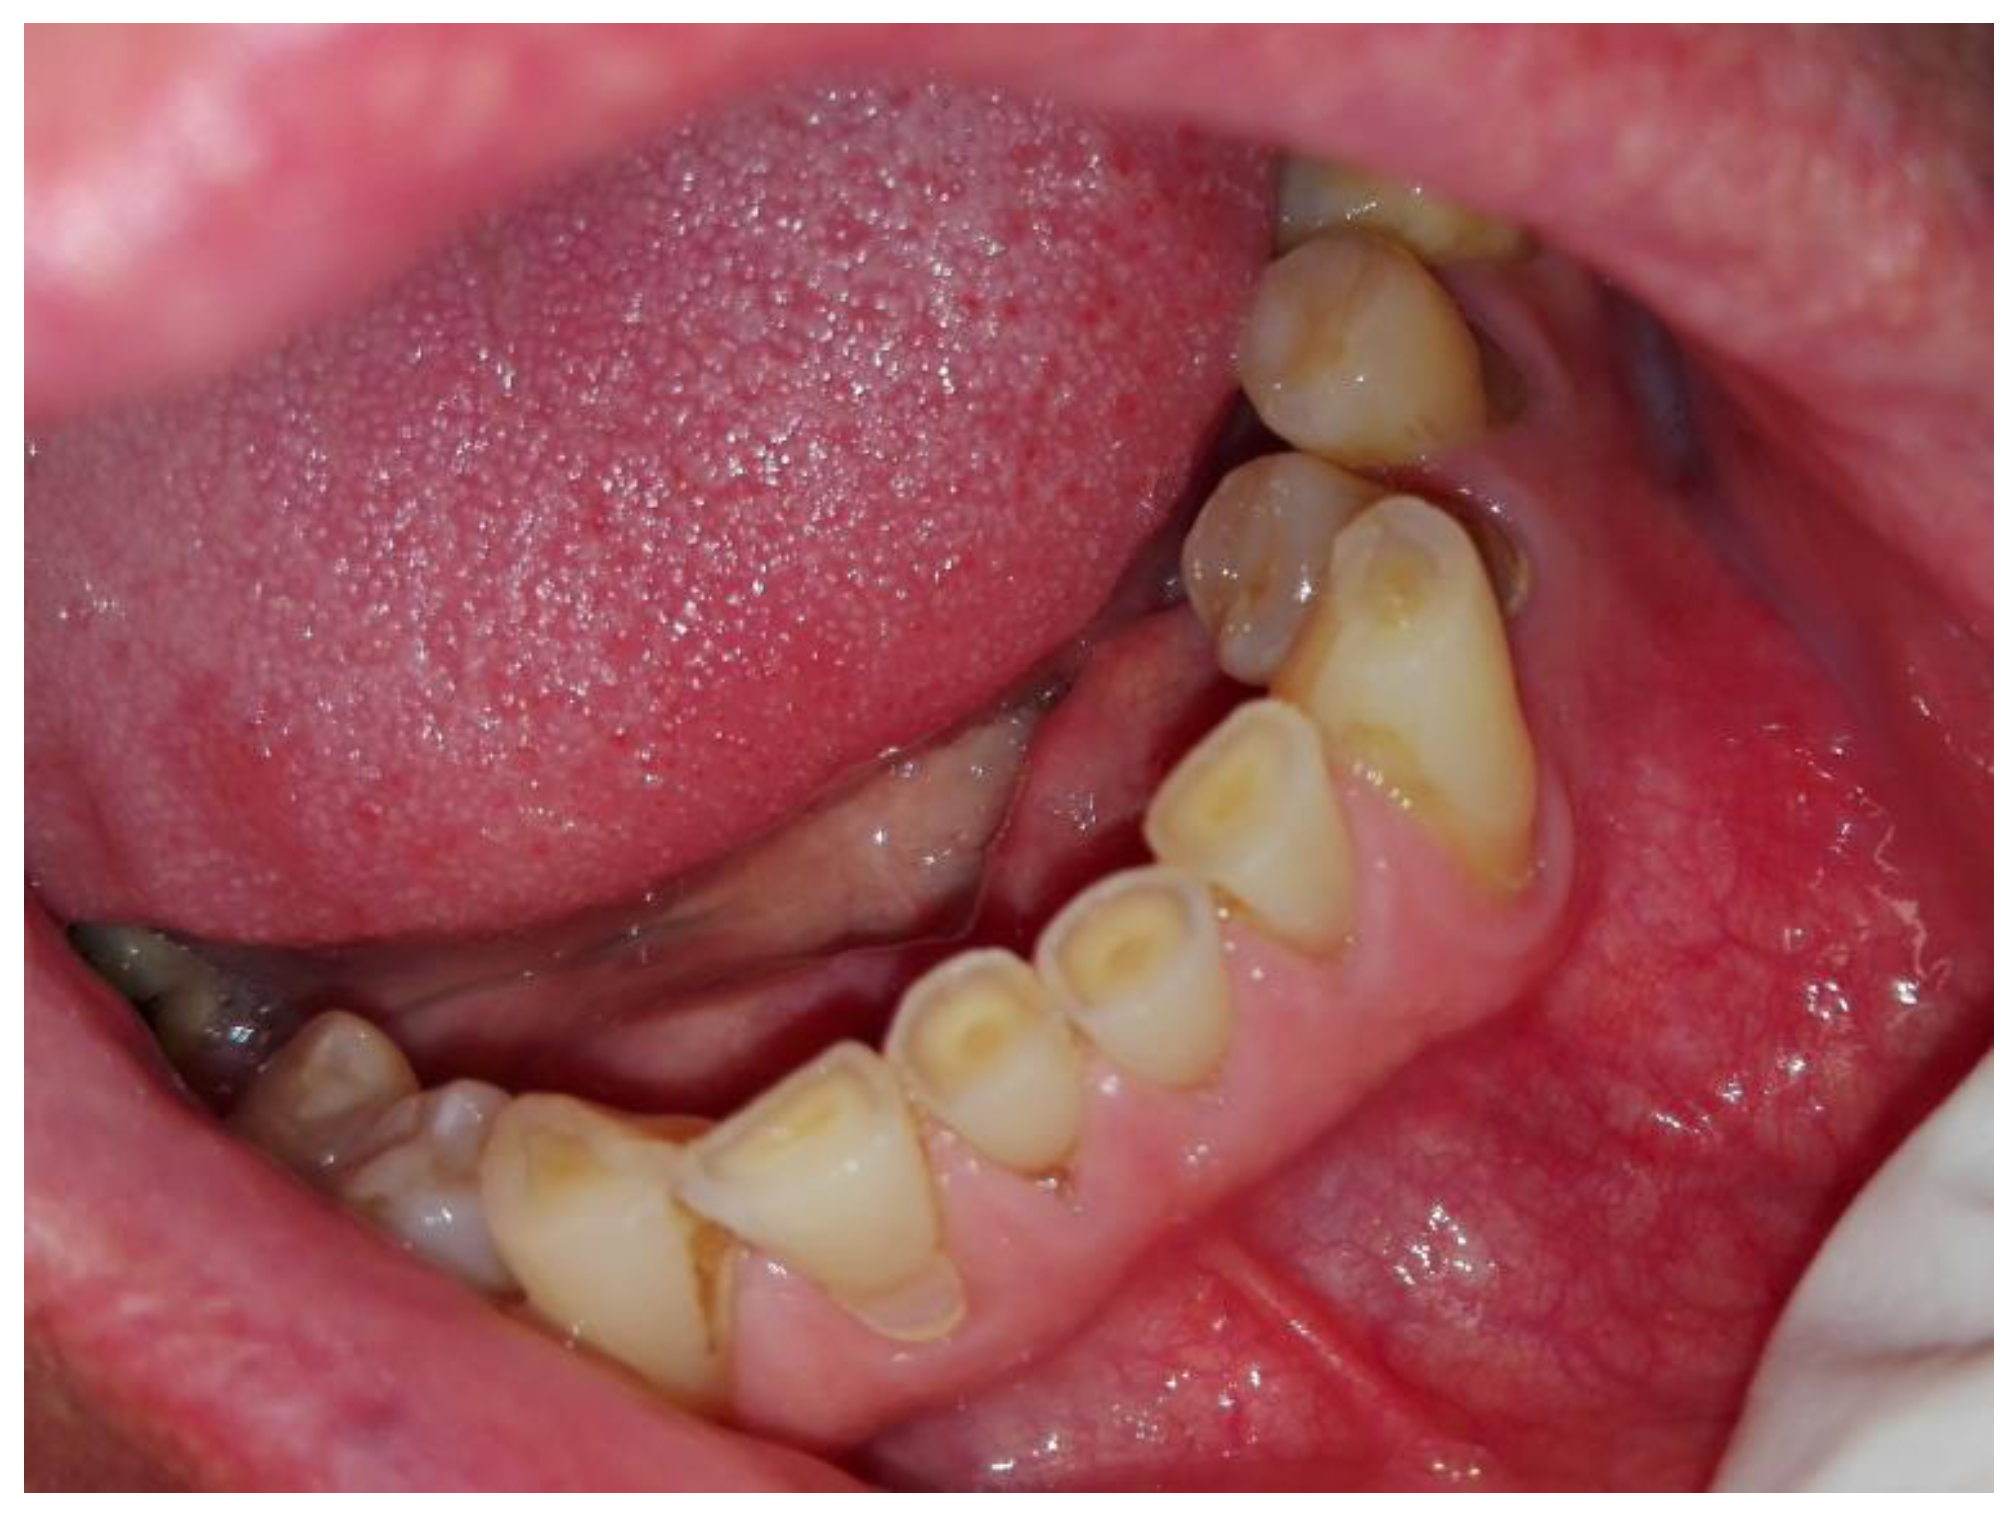

Further examination revealed extensive vestibular swelling ranging from teeth 32–35 and crepitation sign, followed by some elevation and fluctuation between teeth 33–34 (Figure 2). The mucosa was unaffected, and tenderness on the palpation was not noted. However, teeth 31–35 mobility was noted. Teeth 34 and 35 were treated endodontically by a local dentist because of the cyst. Teeth 33–43 remained vital and responsive to cold stimuli. There were no neurological deficiencies related to either cranial nerves or the trigeminal (no Vincent sign) or facial nerves (no palsy). The intraoral photograph reveals good hygiene, with some visible swelling in the anterior portion of the mandible (Figure 3 and Figure 4).

Figure 3. Axial CBCT scans. A great bone dehiscence in the labial part of the bone is noticeable.

Figure 4. The scope of cystic lesion in CBCT.